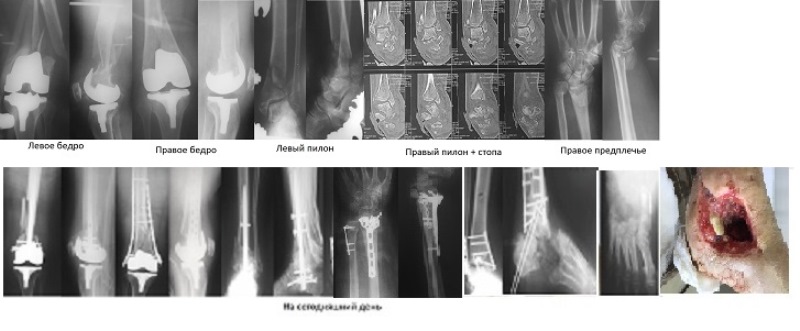

Пациентка 68 лет. Политравма.

В отделении на лечении находится пациентка 68 лет. Травма в результате

ДТП в конце октября 2015 года. Перипротезный перелом правого бедра,

перипротезный перелом левого бедра. Закрытый перелом пилона левой

голени. Закрытый перелом дистального метаэпифиза обеих костей правого

предплечья.

Открытый перелом пилона правой голени, пяточной кости правой стопы

открытый подтаранный вывих правой стопы, открытый переломовывих костей

стопы в суставе Шопара.

При поступлении АВФ стержневые на н/конечности. Перипротезные переломы

оперированы после стабилизации состояния на 8 сутки после поступления.

Левый пилон - на КТ взрывной характер перелома - принято решение

выполнить артродез. Выполнен после спадения отека стержнем Multiloс.

Предплечье - VCP + T образная.

Правая голень - стопа. После ПХО, устранения вывиха в подтаранном

суставе и АВФ стабилизации при поступлении рана велась открыто.

Вторичная хирургическая обработка - секвестрнекрэтомия. Остеосинтез

перелома м/берцовой, б/берцовой костей пластинами, VAC дренирование. За

время лечения еще 3 раза ВХО. На сегодняшний день локальная картина на

фото. Отделяемое серозное, явного гноя нет. R-гр и локально -

практически отсутствует средний отдел стопы: 1/2 таранной кости, 1/2

пяточной кости, предплюсна отсутствует практически полностью.

И вопрос к коллегам - есть ли смысл бороться за стопу?

Если ампутация то какой уровень предпочтительней?

Стоит ли рассматривать ампутацию по типу Пирогова с одновременным

артродезированием г/стопного сустава?